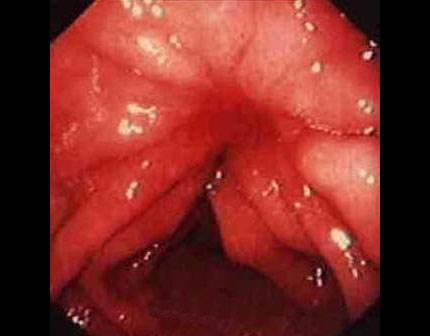

痔瘡是一種常見的肛腸疾病,雖然大多數情況下并不會引發癌變,但長期忽視可能導致病情惡化,了解痔瘡癌變的前兆,及早發現并采取相應措施至關重要,本文將詳細介紹痔瘡癌變的10個前兆,以幫助讀者更好地預防和治療痔瘡。

痔瘡癌變是指痔瘡長期未得到有效治療,導致細胞異常增生,最終演變為癌癥的過程,其發生原因主要包括長期慢性炎癥刺激、不良生活習慣、遺傳因素等,了解這些原因有助于我們更好地預防痔瘡癌變。

痔瘡癌變的10個前兆

1、痔瘡疼痛加劇:痔瘡患者如感覺疼痛逐漸加劇,可能是癌變的一個信號。

2、痔瘡出血:長期痔瘡出血,尤其是出現持續性出血時,應警惕癌變的可能。

3、痔瘡體積變化:如痔瘡體積在短時間內迅速增大,可能是癌變的征兆。

4、排便習慣改變:如排便頻率增加或減少,以及出現便秘與腹瀉交替的情況,可能與痔瘡癌變有關。

5、肛門不適:出現肛門墜脹、異物感等癥狀時,應考慮痔瘡癌變的可能性。

6、消瘦和乏力:如體重迅速下降、乏力等全身癥狀出現時,可能是痔瘡癌變的警示信號。

7、淋巴結腫大:如出現腹股溝或盆腔淋巴結腫大,可能與痔瘡癌變有關。

8、食欲減退:長期食欲減退,尤其是伴有上述癥狀時,應警惕痔瘡癌變。

9、肛周瘙癢:肛周瘙癢可能是痔瘡炎癥的表現,長期不緩解可能發展為癌變。

10、便血顏色變化:如便血顏色由鮮紅色變為暗紅色或混合有黏液,應引起重視。

了解這些前兆對于早期發現痔瘡癌變具有重要意義,一旦發現以上癥狀,患者應立即就醫,進行肛門鏡檢查、活檢等確診,早期發現和治療痔瘡癌變,可以提高治愈率,降低復發風險,保持良好的生活習慣、定期進行體檢、積極治療痔瘡等預防措施至關重要。